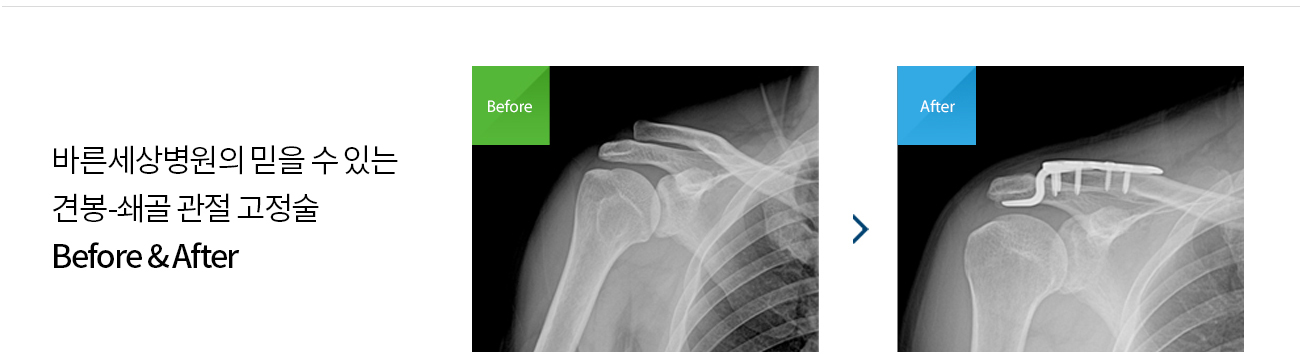

갈고리(hook) 모양의 금속판과 나사를 이용하여 고정하는 방법

이 수술 후에는 견봉-쇄골 관절에 안정성을 높일 수 있습니다.